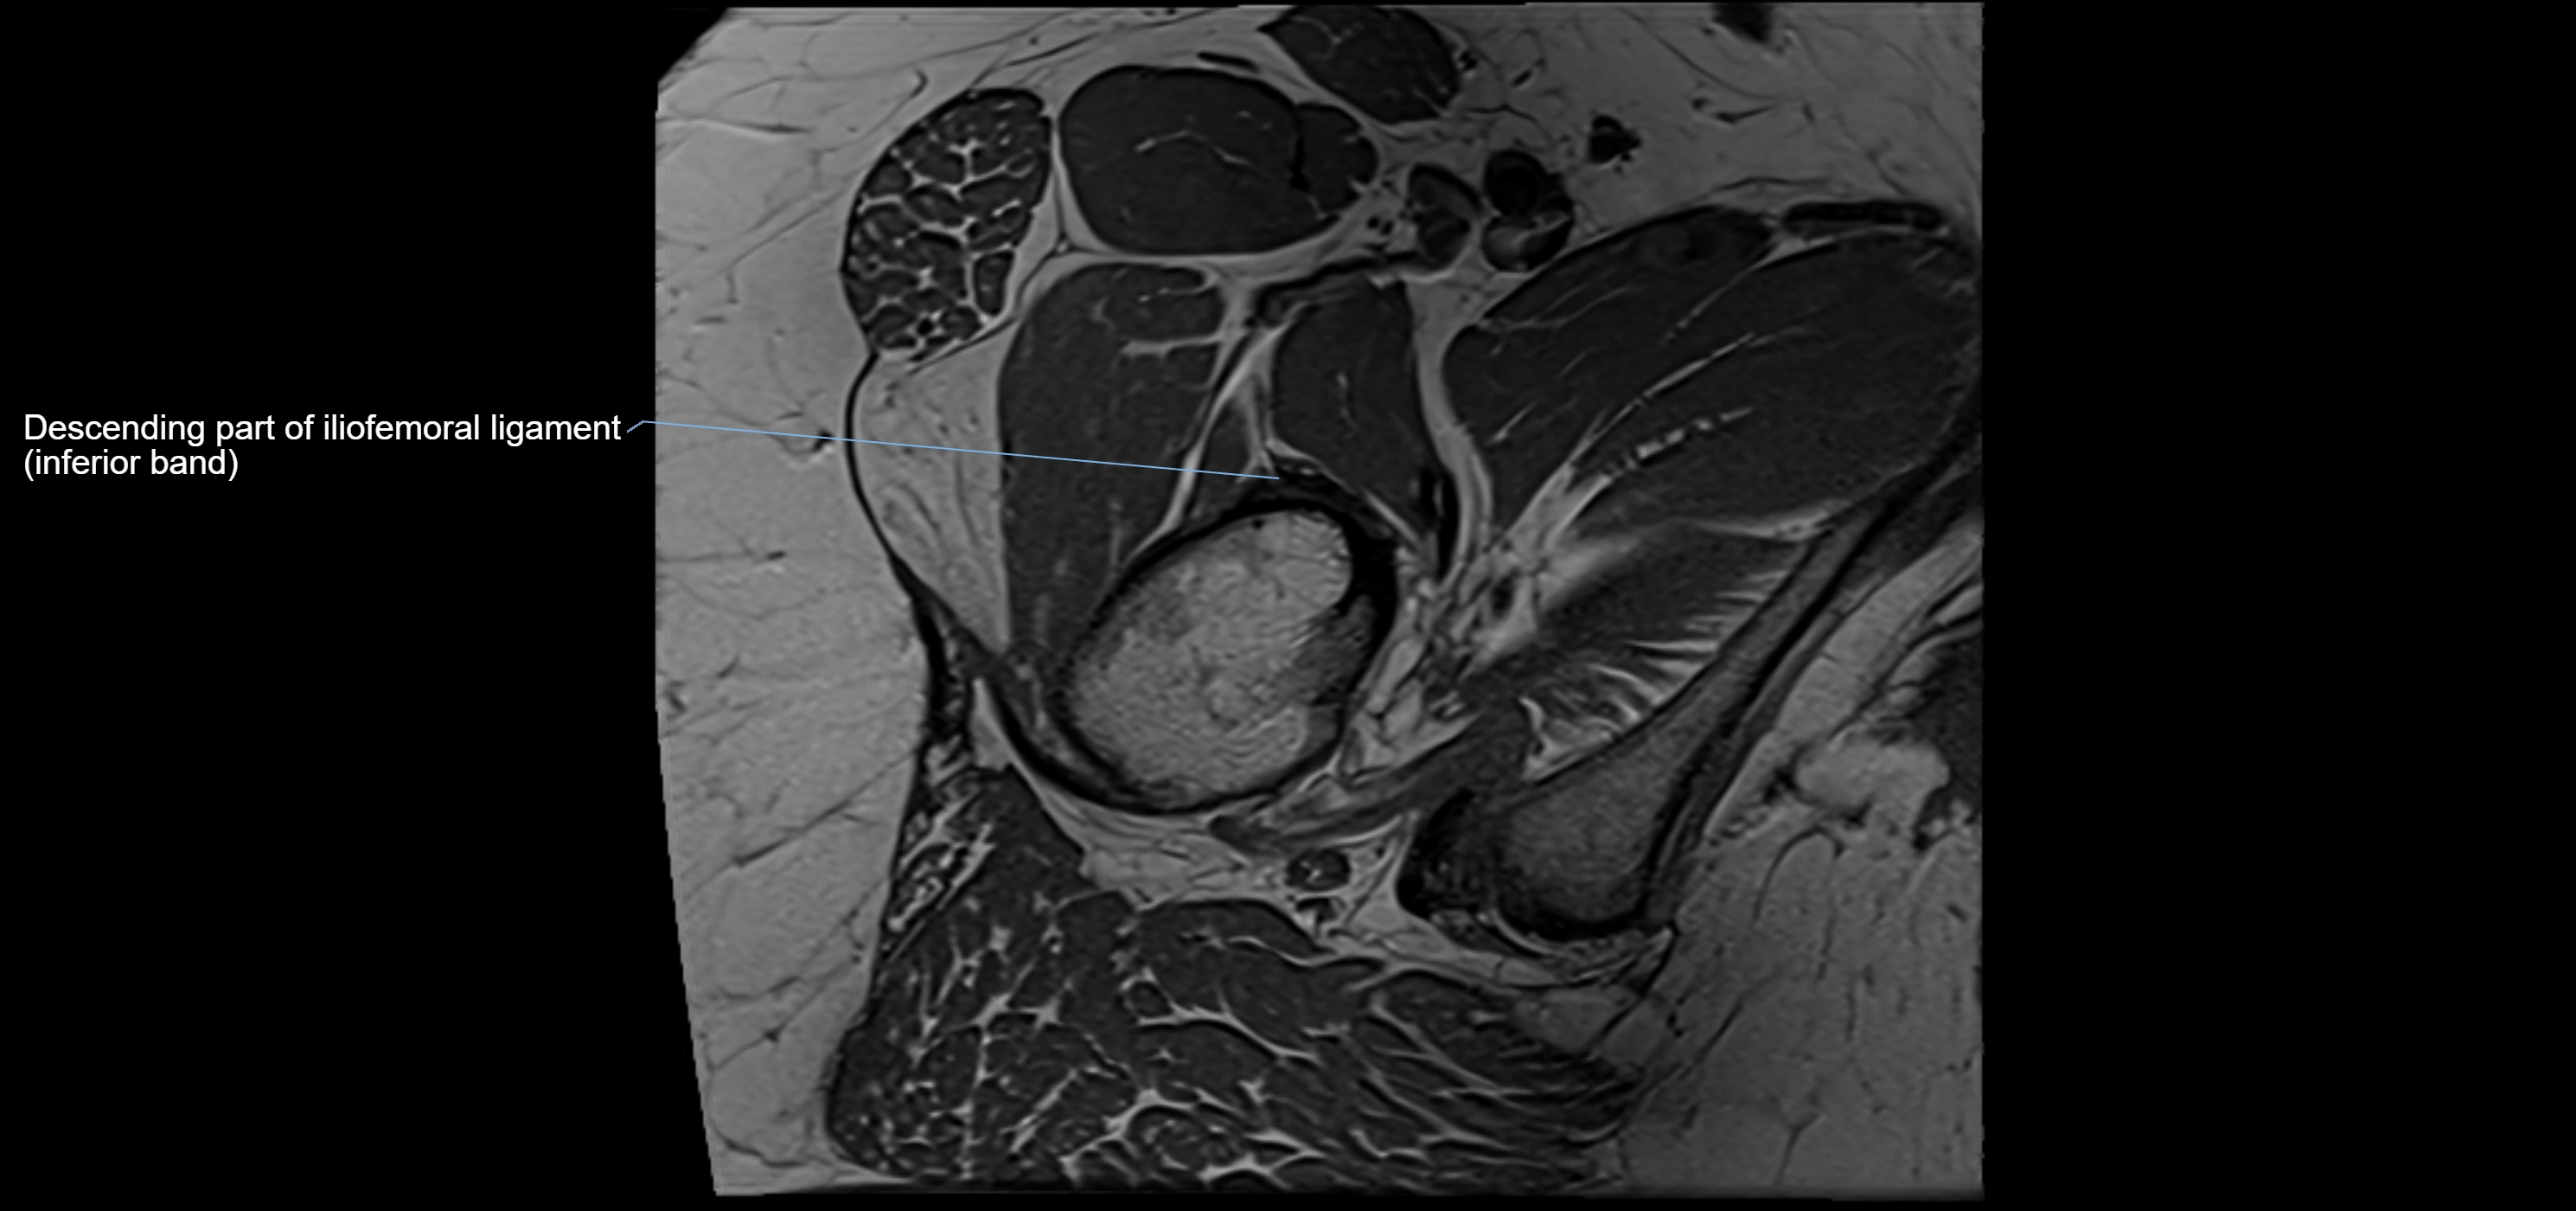

MRI image

image